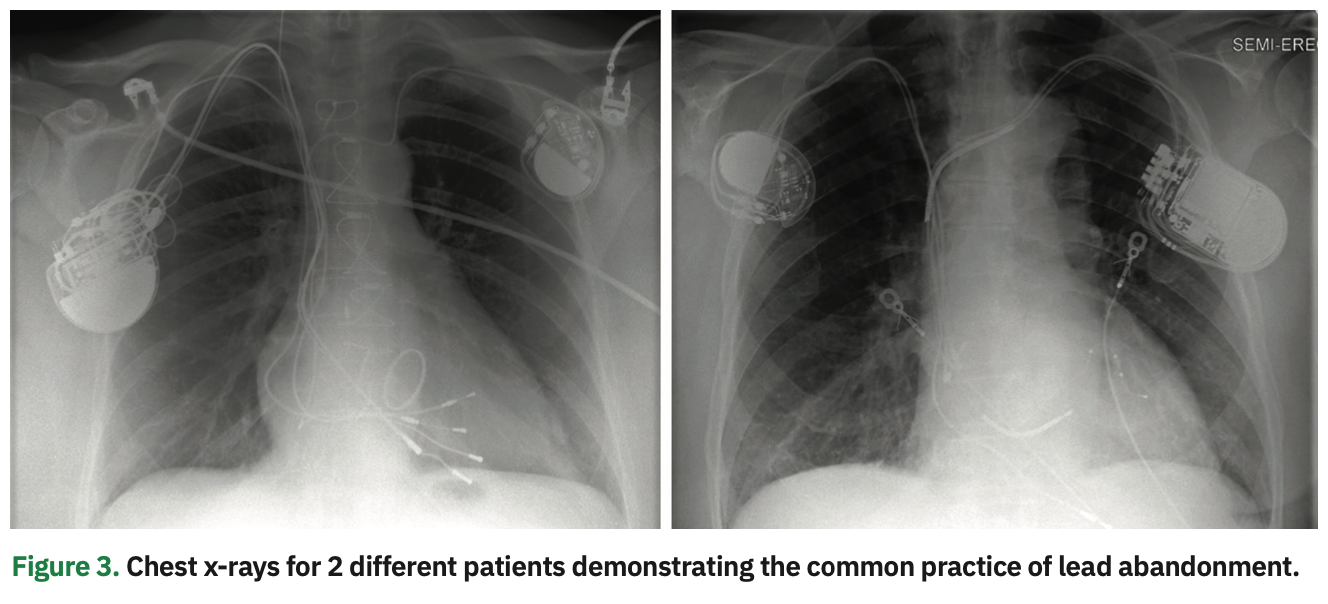

In patients with CIED-related infections, complete removal of all components of the infected device and leads is necessary to eradicate the source of infection.1 On the other hand, in patients undergoing CIED upgrades or lead revisions, extraction of malfunctioning or superfluous leads is not a must, and decisions related to extraction versus abandonment of leads in these cases remain controversial. While the strategy of lead abandonment obviates TLE procedural risks, it carries short- and long-term risks related to increased risk of venous occlusion in the setting of high lead burden, potential for lead–lead interaction, and the impact of multiple leads crossing the tricuspid valve resulting in valvular regurgitation or functional stenosis. In addition, lead abandonment can preclude magnetic resonance imaging. Importantly, the future risks of potential lead extraction (eg, for CIED-related infections) need to be considered in lead abandonment. The presence of previously abandoned leads has been shown to increase the complexity and risk of the TLE procedure given the increasing lead dwell and lead-tissue adherence.3 Under such circumstances, abandonment might mean that extraction of aged leads is only postponed, while lead removal at an earlier time might pose lower procedural risks.

As a consequence, TLE procedures have been considered a category of high-risk interventions, mandating the immediate availability of a multidisciplinary team including a cardiothoracic surgeon, cardiac anesthesiologist, perfusionist, and nursing personnel. This has resulted in increased procedural cost, inefficiency, and resource utilization that are not be feasible at many institutions. The increased procedure complexity has significantly curtailed incorporation of TLE programs beyond a relatively limited number of experienced lead management centers, and hence, there is a limited proliferation of TLE skills among EP trainees. Furthermore, access to care has been hindered for many patients who would benefit from lead extraction for noninfectious indications. Not infrequently, these patients are managed by leaving the nonfunctional leads and adding new leads on the same or contralateral side with no attempt at removing the lead that otherwise could be removed with very minimal added risk. In fact, it is estimated that almost 1 in every 4 patients requiring extraction for CIED infection had a previously abandoned lead in place, a manifestation of the common practice of lead abandonment (Figure 3).3